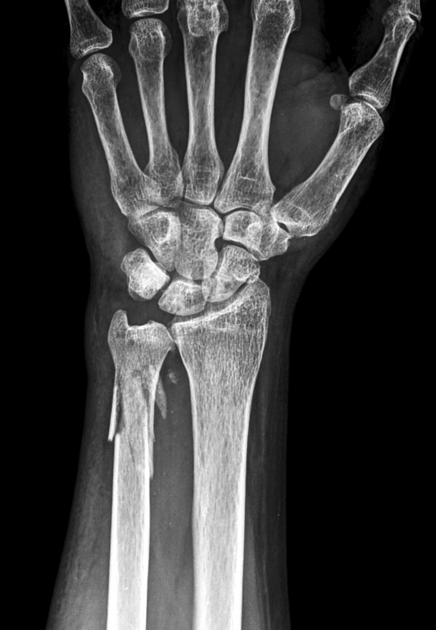

Expand your clinical knowledge with WikiSM.org —a comprehensive resource for sports medicine, MSK exams, and rehabilitation—and MedEdCases.com for real-world, case-based emergency medicine learning